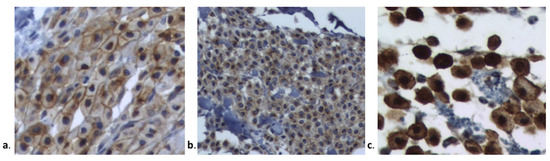

KIT protein localization was determined in all MCTs by microscopic examination. The KIT staining patterns are presented in Figure 1 and Table 4. Most MCTs in groups IM and VP were classified according to the Kit 2 pattern (61.50% and 63.63%, respectively). The KIT pattern did not differ significantly between groups (p = 0.999).

Figure 1. Kit staining patterns according to Kiupel et al., 2004 [19] (a). Kit I: membrane-associated staining, (b). Kit II: focal to stippled cytoplasmic staining with decreased membrane-associated staining, and (c). Kit III: diffuse cytoplasmic staining.